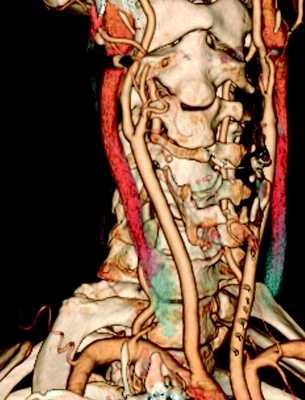

Компьютерная томография магистральных артерий головы, шеи и верхних конечностей

Контрастная компьютерная томографическая ангиография является очень информативным методом диагностики сосудистой патологии. В компьютерной томографии используется сочетание высокотехнологичного рентгеновского сканера и мощная компьютерная обработка, чтобы обеспечить детальное, 3D изображение кровеносных сосудов в головном мозге и шее. КТ - ангиография предоставляет врачу исчерпывающую объемную информацию о строении сосудов, наличии сужений или аневризм, особенностях кровообращения головного мозга.

Поскольку в Инновационном сосудистом центре занимаются высокотехнологичным лечением заболеваний сонных и позвоночных артерий, нам необходима точная диагностика сосудистой патологии мозговых артерий.

Исследования магистральных артерий шеи и головы мы проводим на стационарной базе нашей клиники в г. Клин, либо в партнерской организации в г. Москва. Сосудистые хирурги нашей клиники прекрасно интерпретируют данные МСКТ - ангиографии и на основании этих данных планируют хирургическое вмешательство. В стационаре мы используем современный 64-срезовый компьютерный томограф, обладающий отличными характеристиками изображений.